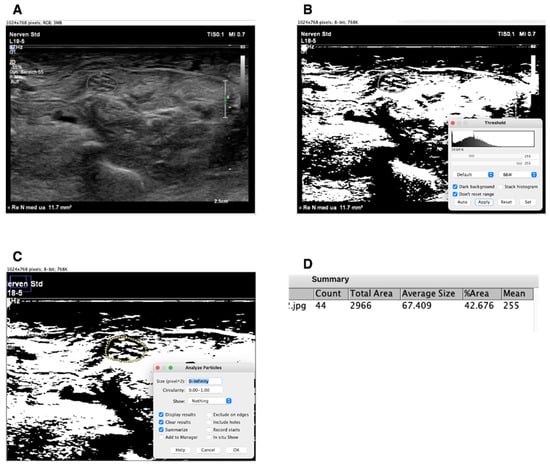

2.3. Evaluation of Echogenicity

Regarding the evaluation of echogenicity, semi-automatic image analysis was performed using ImageJ, as also described previously in Fisse et al. [11], and the fraction of black was quantified. For this purpose, the nerves were marked during the examination, manually outlined, and then converted to 8-bit. Each pixel appears in a range between 0 (black) and 255 (white). Subsequently, an automatic histogram segments the grey levels of the image into black and white pixels using the threshold function. Finally, the hyperechogenic fraction, i.e., the white pixels, can be calculated proportionally as a percentage. The difference to 100 represents the fraction of black. An example is shown in Figure 1.

Figure 1. Analyzing ultrasound pictures in Image J. (A) = median nerve (position lower arm) in a raw ultrasound picture; (B) = the same image converted to 8-bit and modifying threshold to black and white. Automatic threshold function is presented in the lower right corner of the picture in the small window; (C) = now the median nerve in the image is bordered by freehand tracing; settings for analysis of the traced particles are shown on the window on the bottoms right; (D) = finished analysis of the traced particle, the result shows the fraction of white in %. The fraction of black is the difference from 100 minus the fraction of white.